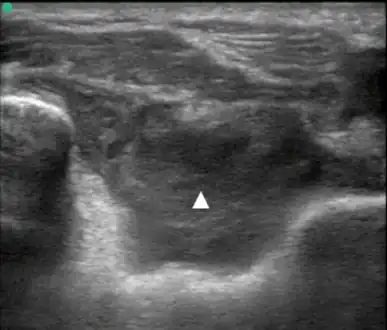

| Lipohemarthrosis (blood and fat in the joint space) seen in a person with a subtle tibial plateau fracture. The arrow indicates a fluid level between the upper fat component and the lower blood component. | |

Posterior transverse view of the elbow with hemarthrosis

Posterior transverse view of the elbow with hemarthrosis -

Synovial Fluid analysis is another method to diagnose Hemarthrosis. It involves a small needle being inserted into the joint to draw the fluid.[8] Reddish-colored hue of the sample is an indication of the blood being present. Imaging tests are normally done. The tests also include MRI, Ultrasound and X-ray test, which give better information about the joint inflammation.[9]